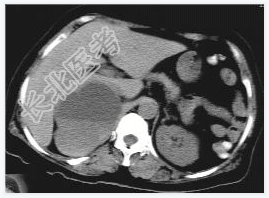

- [材料题] 女性,59岁,胸闷、头晕2天,呈持续性,伴呕吐,以进食后明显。发现“高血压”10年,“糖尿病”2年。体格检查:血压70~210/30~120mmHg。

- 简答题1、该病患诊断是什么?

- 简答题2、鉴别诊断有哪些?

- 简答题3、右肾上腺嗜铬细胞瘤囊变的定义是什么?

- 简答题4、右肾上腺嗜铬细胞瘤囊变的临床意义是什么?

- 简答题5、右肾上腺嗜铬细胞瘤囊变的诊断和治疗上需要注意哪些事项?